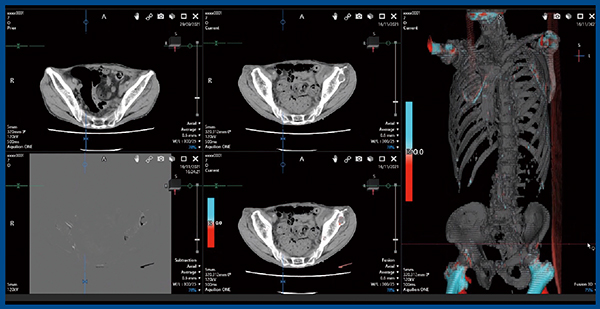

また,変化があるものの気づきにくかった症例も提示する。症例4は,70歳代,男性の尿管がんで,左腸骨に溶骨型転移が認められた(図5)。しかし,3Dフュージョン画像では周囲に強いアーチファクトがあり,サブトラクション画像の方が病変に気づきやすいと思われた。3Dフュージョン画像でアーチファクトが生じやすい部位としては,動きの大きな肩甲骨や上腕骨,大腿骨などがある。そのほか,転移との鑑別が困難だったものとして,脊椎の圧迫骨折やSchmorl結節,肋骨の良性骨折,肋軟骨の骨化などがある。さらに,転移の頻度は多くないものの左肩甲骨に転移が見られた症例も経験しており,画像にアーチファクトが生じている場合は,病変に気づきにくくなる可能性がある。

図5 症例4:70歳代,男性,尿管がん